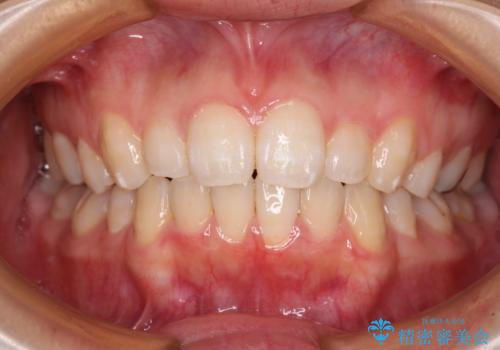

費用を抑えた抜歯矯正 口元の突出感の改善

- 口元の突出感を気にして来院された患者様です。

左右ともに上顎奥歯が外を向き、下顎奥歯が内側に倒れているシザーズバイトであったため、補助装置により改善することとしました。

上下の咬み合わせは、下顎に対して上顎が相対的に前方にあったため、奥歯のシザーズバイト改善後に上顎左右第一小臼歯2本を抜歯し、上顎前突を改善していくこととしました。

左側の咬み合わせと上下正中の位置をコントロールするために時間がかかりましたが、事前に思い描いた通りの歯列に整い、患者様には大変満足していただきました。